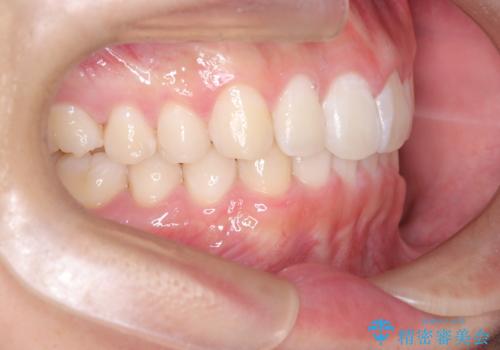

- 歯のデコボコと過蓋咬合を主訴に来院された患者様です。

アーチの拡大とIPRを行い非抜歯で治療を行いました。

歯を抜かずに叢生(デコボコ歯列)と過蓋咬合を改善する事が出来ました。

インビザラインによる治療でも十分に美しい歯並びを実現でき、患者様にも大変ご満足いただけました。